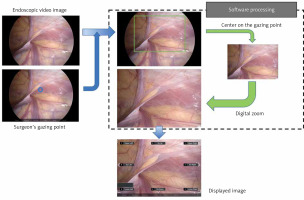

An overview of the system is shown in Photo 1 [5]. We used the Tobii Eye Tracker 4C system (Tobii Technology AB, Danderyd, Sweden). This infrared-based device calculates the direction of the point of gaze using the vector between the pupil center and the corneal reflection produced by the device. The eye tracking device was fixed to a flat panel display and the surgeon’s gaze point on the display was acquired. The video image is processed by the computer software according to the voice command and displayed on the flat panel display in real time.

Photo 1

Steps taken by the developed computer software system to obtain a digitally zoomed image for display, centered on the surgeon’s gaze point